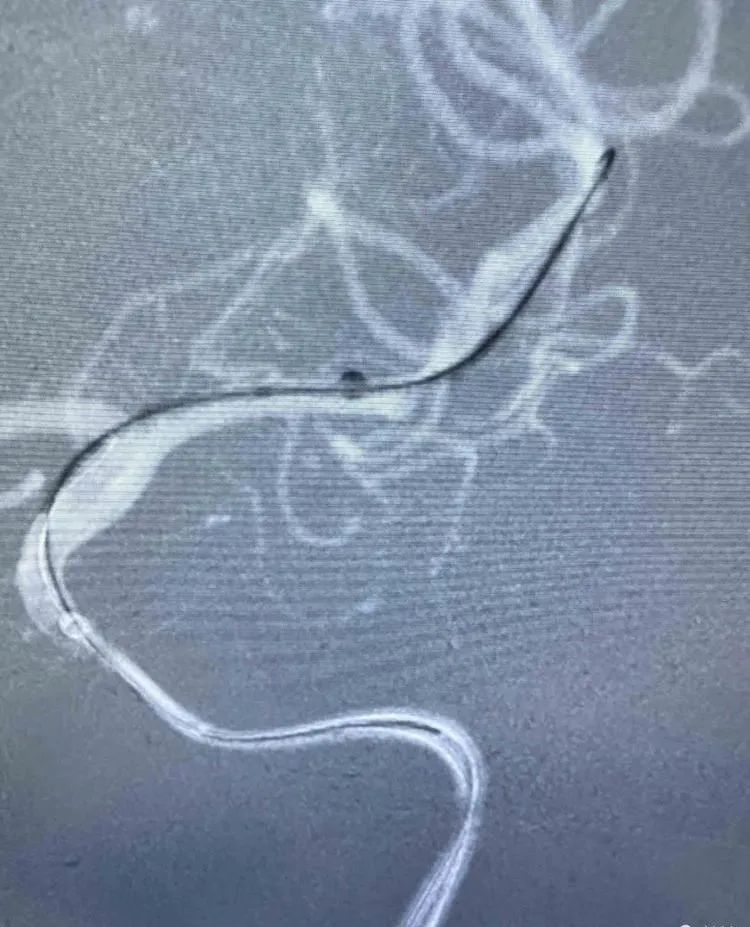

治疗过程